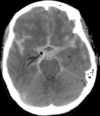

Label.

epidural hematoma

middle meningeal artery